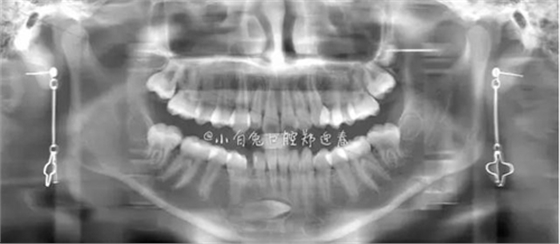

本案:患兒,女,14歲,因牙齒矯正來院,檢查見83滯留,43未見萌出,拍片發(fā)現(xiàn):43埋伏阻生于31、41、42根尖下方,按照正畸診療計劃,擬行43拔除術。

全景片